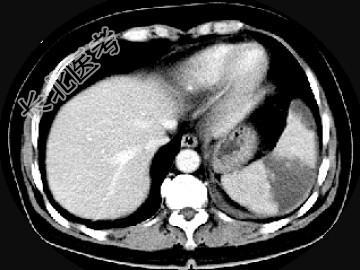

- 单项选择题女,54岁, 左上腹痛,CT检查如图, 最可能的诊断是 ( )

A、脾淋巴瘤

B、脾脓肿

C、脾梗死

D、脾血管瘤

E、脾转移癌